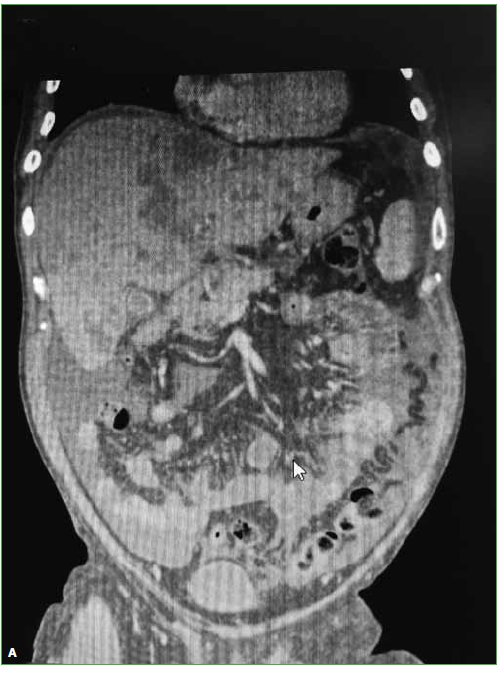

23. Yamaguchi T, Suzuki S, Ishiiwa H, Yamato M, Ueda Y. Schmorl’s node developing in the lumbar vertebra affected with metastatic carcinoma: correlation magnetic resonance imaging with histological findings. Spine 2003;28(24):E503-E505. https://doi.org/10.1097/01.BRS.0000099388.63504.4D

24. Borad MJ, Saadati H, Lakshmipathy A, Campbell E, Hopper P, Jameson G, et al. Skeletal metastases in pancreatic cancer: a retrospective study and review of the literature. Yale J Biol Med 2009;82(1):1-6. https://www.ncbi.nlm.nih.gov/pmc/articles/PMC2660584/

25. Pneumaticos SG, Savidou C, Korres DS, Chatziioannou SN. Pancreatic cancer’s initial presentation: back pain due to osteoblastic bone metastasis. Eur J Cancer Care 2010;19(1):137-40. https://doi.org/10.1111/j.1365-2354.2007.00920.x